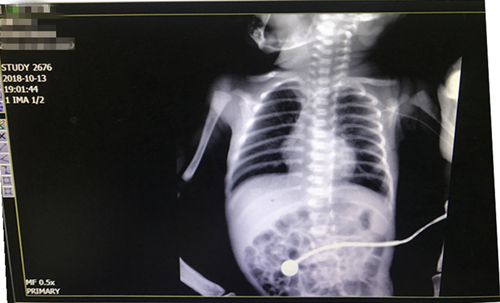

该技术操作过程较复杂,操作技术水平要求极高,置管过程中随时可能会出现呼吸、心跳骤停等危急情况。针对这一情况,在杨护士长到来之前,科室护理团队已将PICC置管需要的物品及抢救药物准备齐全,并制定出各种应急措施。新生儿科护士车棠和王昱与特邀专家分工协作,一针穿刺成功,同时急请放射科配合拍胸片确定导管位置,成功为该患儿实施了PICC置管术。此置管术为乐鱼手机站入口首例新生儿PICC置管新技术。